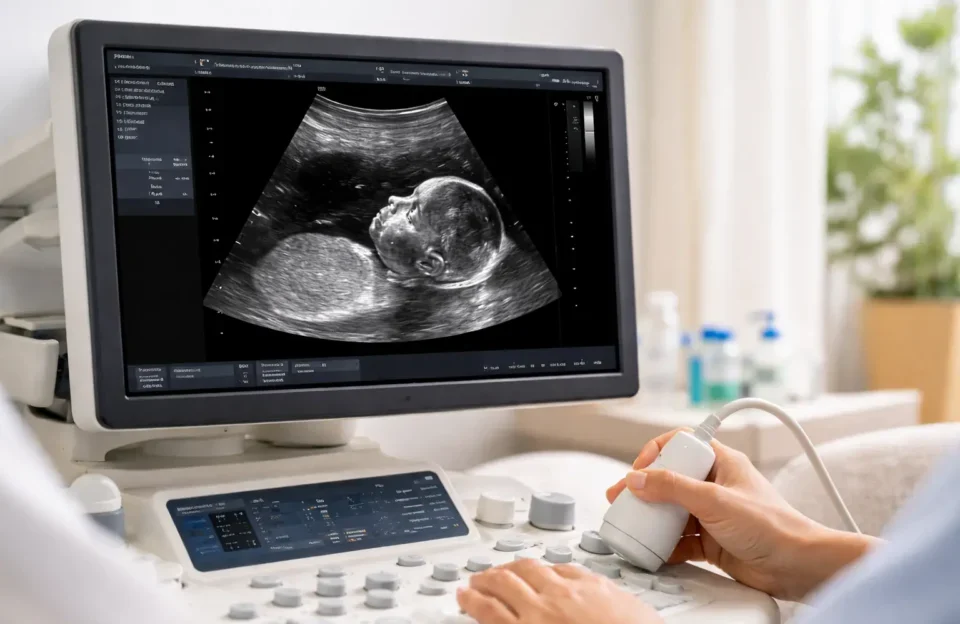

A translucência nucal é um exame de ultrassom que mede a quantidade de líquido acumulado na região da nuca do bebê. Essa medida, realizada entre 11 e 14 semanas de gravidez, ajuda a avaliar o risco de o bebê ter alterações cromossômicas, como síndrome de Down (trissomia do 21), síndrome de Edwards (trissomia do 18) ou síndrome de Patau (trissomia do 13).

Durante o ultrassom, o médico mede a espessura da camada de líquido na parte de trás do pescoço do bebê. Todos os bebês têm algum líquido nessa região, mas quando a quantidade é maior que o esperado para a idade gestacional, pode indicar risco aumentado de problemas. Portanto, a translucência nucal funciona como um sinalizador inicial.

Como É Feito o Exame

O exame é feito por ultrassom, geralmente abdominal, mas pode ser transvaginal para melhor visualização. O bebê precisa estar em posição específica (perfil neutro) para a medição precisa. A medida é tomada três vezes, usando-se a maior delas.

O exame dura 20-30 minutos. Às vezes o bebê não coopera, e é preciso esperar ele se mexer. Não é necessário preparo especial, bexiga cheia ou jejum. O exame não causa dor.